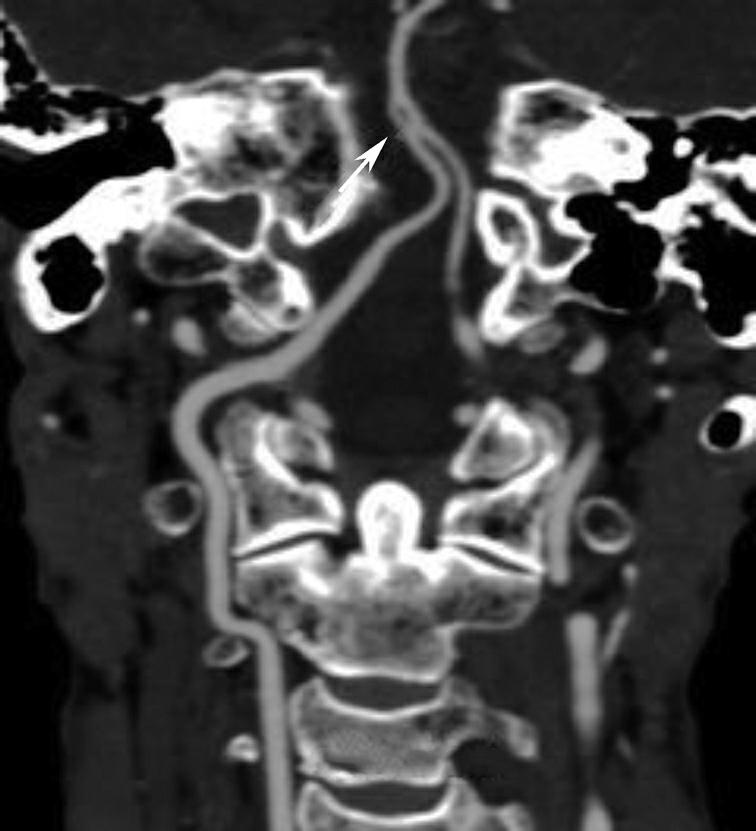

永存三叉动脉是颈内动脉海绵窦段与基底动脉之间的胚胎性吻合,为颈内动脉系统与椎基底动脉系统之间最常见的异常交通,是根据它伴行的颅神经而命名的。其他异常吻合包括永存听动脉、永存舌下动脉及永存寰前节间动脉(图1-2-79)。

图1-2-79 永存三叉动脉

A、B.异常吻合支沟通至右侧海绵窦(箭);基底动脉(长箭)